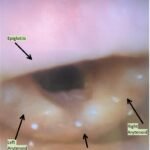

This is a case report of a 55-year-old woman with a past medical history of hypertension who presented to the emergency department with upper lip and cheek swelling isolated to the right side of her face. She was on lisinopril for several years and had never had an episode of swelling in the past. Her vital signs were stable. However, on reassessment, the patient’s right sided swelling progressed to the entire upper lip and she complained of swelling in her submandibular space. Although no swelling was appreciated to the submandibular space on physical exam, and the patient still did not have any signs or symptoms of respiratory distress, the decision was made to use a fiberoptic laryngoscope to evaluate her airway. Fiberoptic laryngoscope showed noticeable laryngeal edema which did not improve after treatment, and the patient was admitted to the medical intensive care unit for close airway observation. This case highlights the use of fiberoptic laryngoscope by emergency physicians in the evaluation of patients with relatively benign appearing angioedema.

ACE-I, angioedema, fiberoptic laryngoscope, laryngeal edema, tranexamic acid.